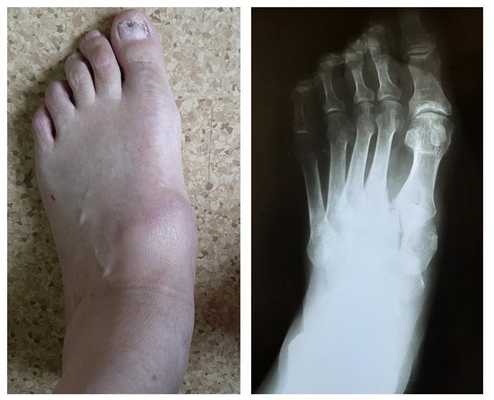

Ниже приведу пример лечения пациента с затарелым вывихом в суставе Лисфранка, которое проходило в стенах нашего отделения.

Пациенты с переломо-вывихами в суставе Лисфранка часто оказываются в ситуации, когда никто из врачей не хочет за них браться. Так случилось и с пациентом Ж. 64 лет, который получил травму ещё в 2001 году, но оперировать его отказались. Боль и деформация прогрессировали, и на протяжении последних 10 лет пациент уже не мог пройти больше 800 метров. Постоянное ношение ортопедических стелек не давало облегчения симптомов.

![вывих в суставе Лисфранка]()

После осмотра в отделении ортопедии №2 ГКБ №13 принято решение о проведении операции – открытому устранению вывиха, артродезе 1-2-3 плюсне-клиновидных суставов, 1 межклиновидного сустава при помощи винтов и пластины, трансартикулярной фиксации спицами 4-5 плюсне-клиновидных суставов.

![вывих в суставе Лисфранка операция]()